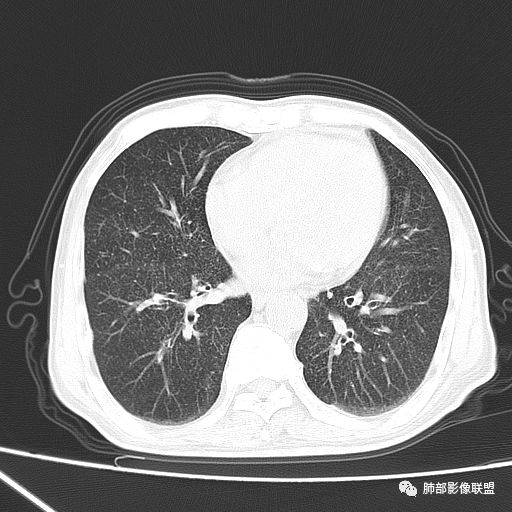

2019-10-20复查CT如下:

两肺弥漫性粟粒样结节伴左上肺小结节,呈三均匀分布,有结核的临床表现,支持血性播散性肺结核。

大小、分布均匀,边缘清楚

细小结节,弥漫,撒米粒样——血道来源

血道来源的病灶,均匀、细微,而且部分有分支状,都符合粟粒型肺结核

急性血行播散型肺结核  两肺广泛分布粟粒大小的结节状密度增高影,具有大小均匀、分布均匀、密度均匀的典型“三均匀”特征,注意急性血播病灶非常小,一般粟粒影直径1~2mm。

病灶密集者出现肺外围血管影不清或减少。

发热初期肺部可缺乏典型影像学改变,1到2周后出现的广泛粟粒结节对诊断具有高度提示作用!